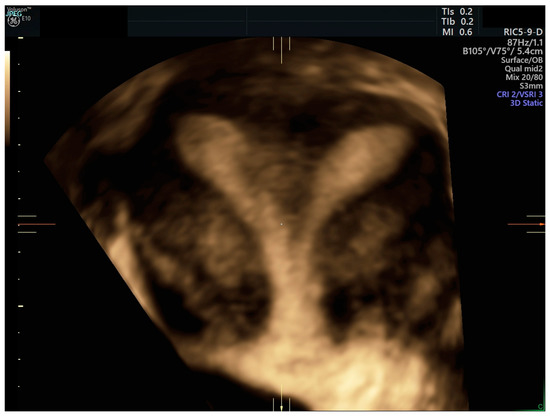

2. Case Report

1. Introduction